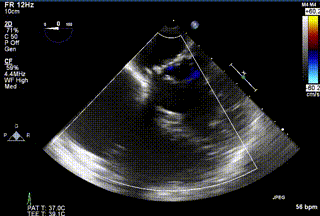

2021年12月24日,復旦大學附屬中山醫(yī)院葛均波院士團隊成功應用LuX-Valve Plus為一例極重度三尖瓣反流(TR)合并房顫、房缺的患者完成了經血管三尖瓣置換術,這是在前基礎上,本周完成的第三例經血管三尖瓣置換手術,葛均波院士、周達新教授等與心外科魏來教授、賴顥教授,心超室的潘翠珍教授、李偉教授及麻醉科的郭克芳教授共同完成了本周手術,均獲得圓滿成功!患者術后超聲顯示無TR,臨床癥狀明顯改善。本周手術的成功也為LuX-Valve Plus救治性臨床研究添上了濃墨重彩的一筆。

三例患者入院后,葛均波院士團隊周達新教授、潘文志教授、張源博士、陳莎莎博士及心超室的潘翠珍教授、李偉教授對患者的情況進行詳細評估和討論,最終決定為三例患者選擇LuX-Valve Plus40mm、50mm和50mm型號的瓣膜進行手術治療。手術后即刻拔除氣管插管,術后患者三尖瓣反流癥狀得到顯著改善,復查心超結果顯示人工三尖瓣瓣膜支架固定穩(wěn)定,瓣葉關閉形態(tài)未見異常,未見明顯反流。